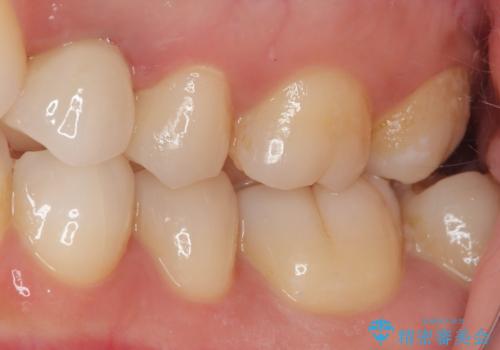

左上小臼歯を抜歯し、矯正治療でスペースを閉じる方法と左上小臼歯を抜歯し、抜歯即時インプラントを行う方法、保存療法を行う方法の治療期間、費用、メリット・デメリットについて説明したうえで治療期間をできるだけ短くしたいという希望があったため抜歯即時インプラント治療を選択されました。

矯正・インプラント・保存治療を含めた総合的な診断によって、患者様に合った選択肢が見つかることがあります。

治療法は一つではありません。お悩みの方は、ぜひ一度ご相談ください。